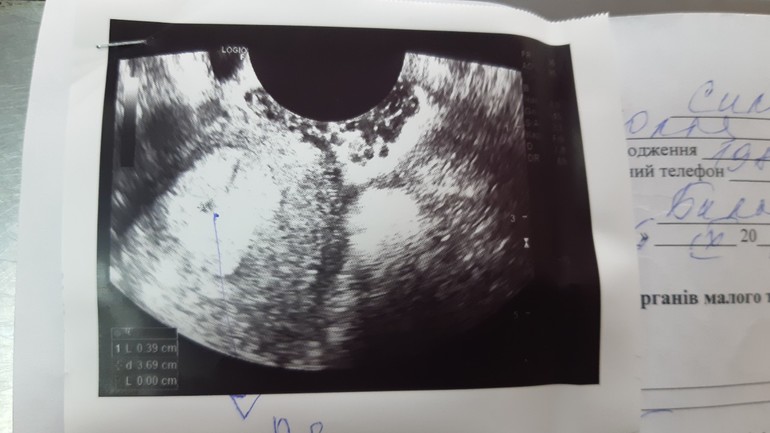

ни одного. пя на узи это темные (черные пятна) окруженные светлой оболочкой

Честно говоря ни одного, визуализация ужасная, но можно предположить, что темное пятнышко на которое указывает стрелка это ПЯ. Других не видно.

Шейка 30мм Грустный день